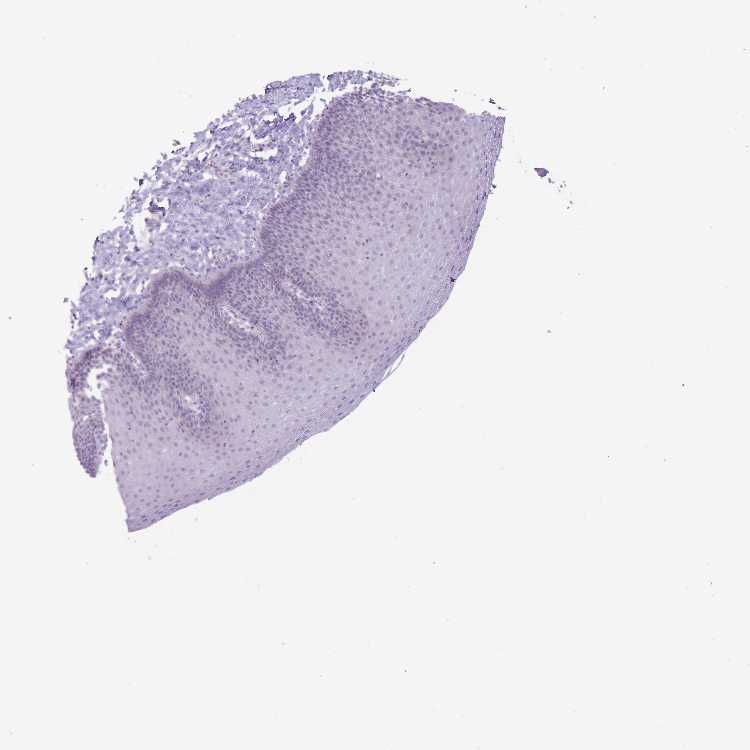

ESOPHAGUS - Antibody stainingi

Antibody staining in the annotated cell types in the current human tissue is reported as not detected, low, medium, or high, based on conventional immunohistochemistry profiling in selected tissues. This score is based on the combination of the staining intensity and fraction of stained cells.

Each image is clickable and will lead to virtual microscopy that enables deeper exploration of all samples and also displays staining intensity scores, fraction scores and subcellular localization as well as patient and tissue information for each sample.

Antibody HPA042632Antibody HPA048484

Squamous epithelial cells MediumNot detected